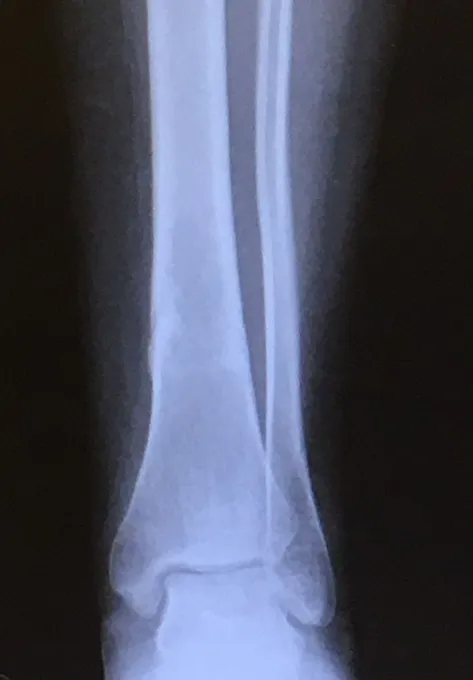

Below, Tibia and Fibula Fracture in a 16-year-old injured skiing. The patient presented to the office 8 days after injury with a displaced fracture. The first 2 films show the displacement in the fracture of the tibia. After an above knee cast is applied, the cast is wedged under fluoroscopy and new xrays show the near perfect reduction of the fracture. The white arrows show the area where the cast is wedged